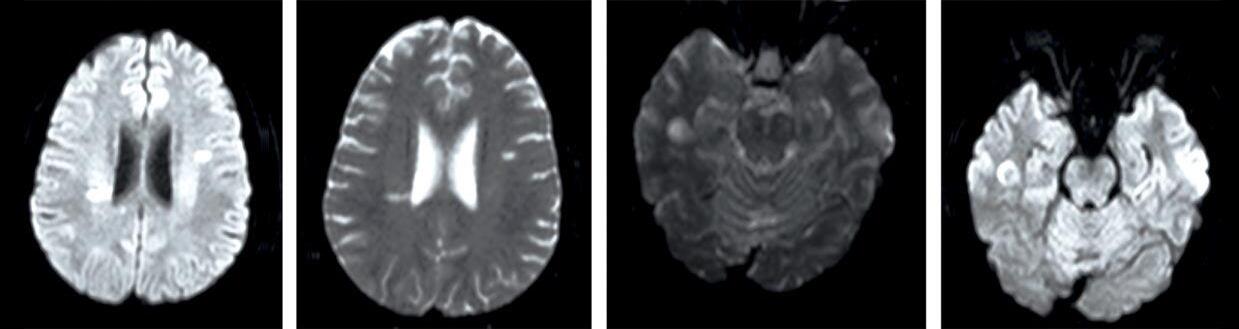

Paciente femenina de 37 años, sin antecedentes patológicos, acude a la guardia oftalmológica por visión borrosa en ambos ojos de cuatro días de evolución, a predominio en su ojo derecho. Refirió que el inicio de los síntomas visuales fue posterior a la realización de un esfuerzo físico.

Al examen oftalmológico, presentó agudeza visual mejor corregida de 20/60 en ojo derecho y 20/30 en ojo izquierdo, sin particularidades en el resto del examen. Por ello, se decidió realizar exámenes complementarios (OCT macular, OCT de capa de fibras y campo visual computarizado 30.2), siendo solo significativo el resultado de la campimetría de ambos ojos.

Según estudios realizados, la campimetría computarizada ayuda a evaluar la gravedad de los ataques y son de importancia para el monitoreo de la eficacia y el alcance de la resolución del ataque espontáneo. Casos con afectaciones no centrales se han evidenciado en 25% de los pacientes diagnosticados, siendo las presentaciones más frecuentes los escotomas altitudinales, cuadrantanopsias, afectaciones de tres cuadrantes del campo visual y las hemianopsias homo o bilaterales. En este caso se puede evidenciar en el ojo derecho hemianopsia temporal incipiente y en el ojo izquierdo arcuato superior.

Ante la sospecha diagnóstica de neuritis óptica atípica, solicitamos laboratorio completo con análisis de anticuerpos AQP4 y anti MOG, resonancia magnética de cerebro, órbita y columna cervical, con y sin contraste. El análisis de los anticuerpos solicitados arrojó un resultado negativo para la totalidad.

Para destacar, en la RMN de órbita se apreciaron múltiples hiperintensidades espontáneas proveniente de la sustancia blanca bihemisférica y en la RMN de columna cervical se hallaron imágenes de hiperintensidad focal en T2 de la de hemi médula derecha, extendiéndose a la altura de C4 y C5, de 24 mm diámetro craneocaudal, compatible con lesión desmielinizante inflamatoria.

Se interpretó el cuadro como un trastorno del espectro de la neuromielitis óptica, por lo que se indicó tratamiento inmediato con pulsos de corticoide intravenoso y ante la falta de respuesta a los mismos, se decidió realizar plasmaféresis, con la que, posterior a cinco ciclos, se evidenció una mejoría de la agudeza visual de ambos ojos a 20/25.

Es importante considerar el principal diagnóstico diferencial, la esclerosis múltiple, siendo la RMN de cerebro crucial para distinguir entre estas entidades clínicas, ya que la presencia de lesiones inespecíficas en la sustancia blanca que no cumplen con los criterios de EM soportan el diagnóstico de NMO, por lo que el pronóstico y el tratamiento difieren considerablemente.

Imagen 4: Resonancia magnética de encéfalo y órbitas (con y sin gadolinio). En pulso FLAIR se aprecian múltiples hiperintensidades espontáneas provenientes de la sustancia blanca bihemisférica, la dominante a nivel temporal derecho, de 12 mm de diámetro, sugestivas de lesiones desmielinizantes. No generan efecto de masa y presentan discreto realce.